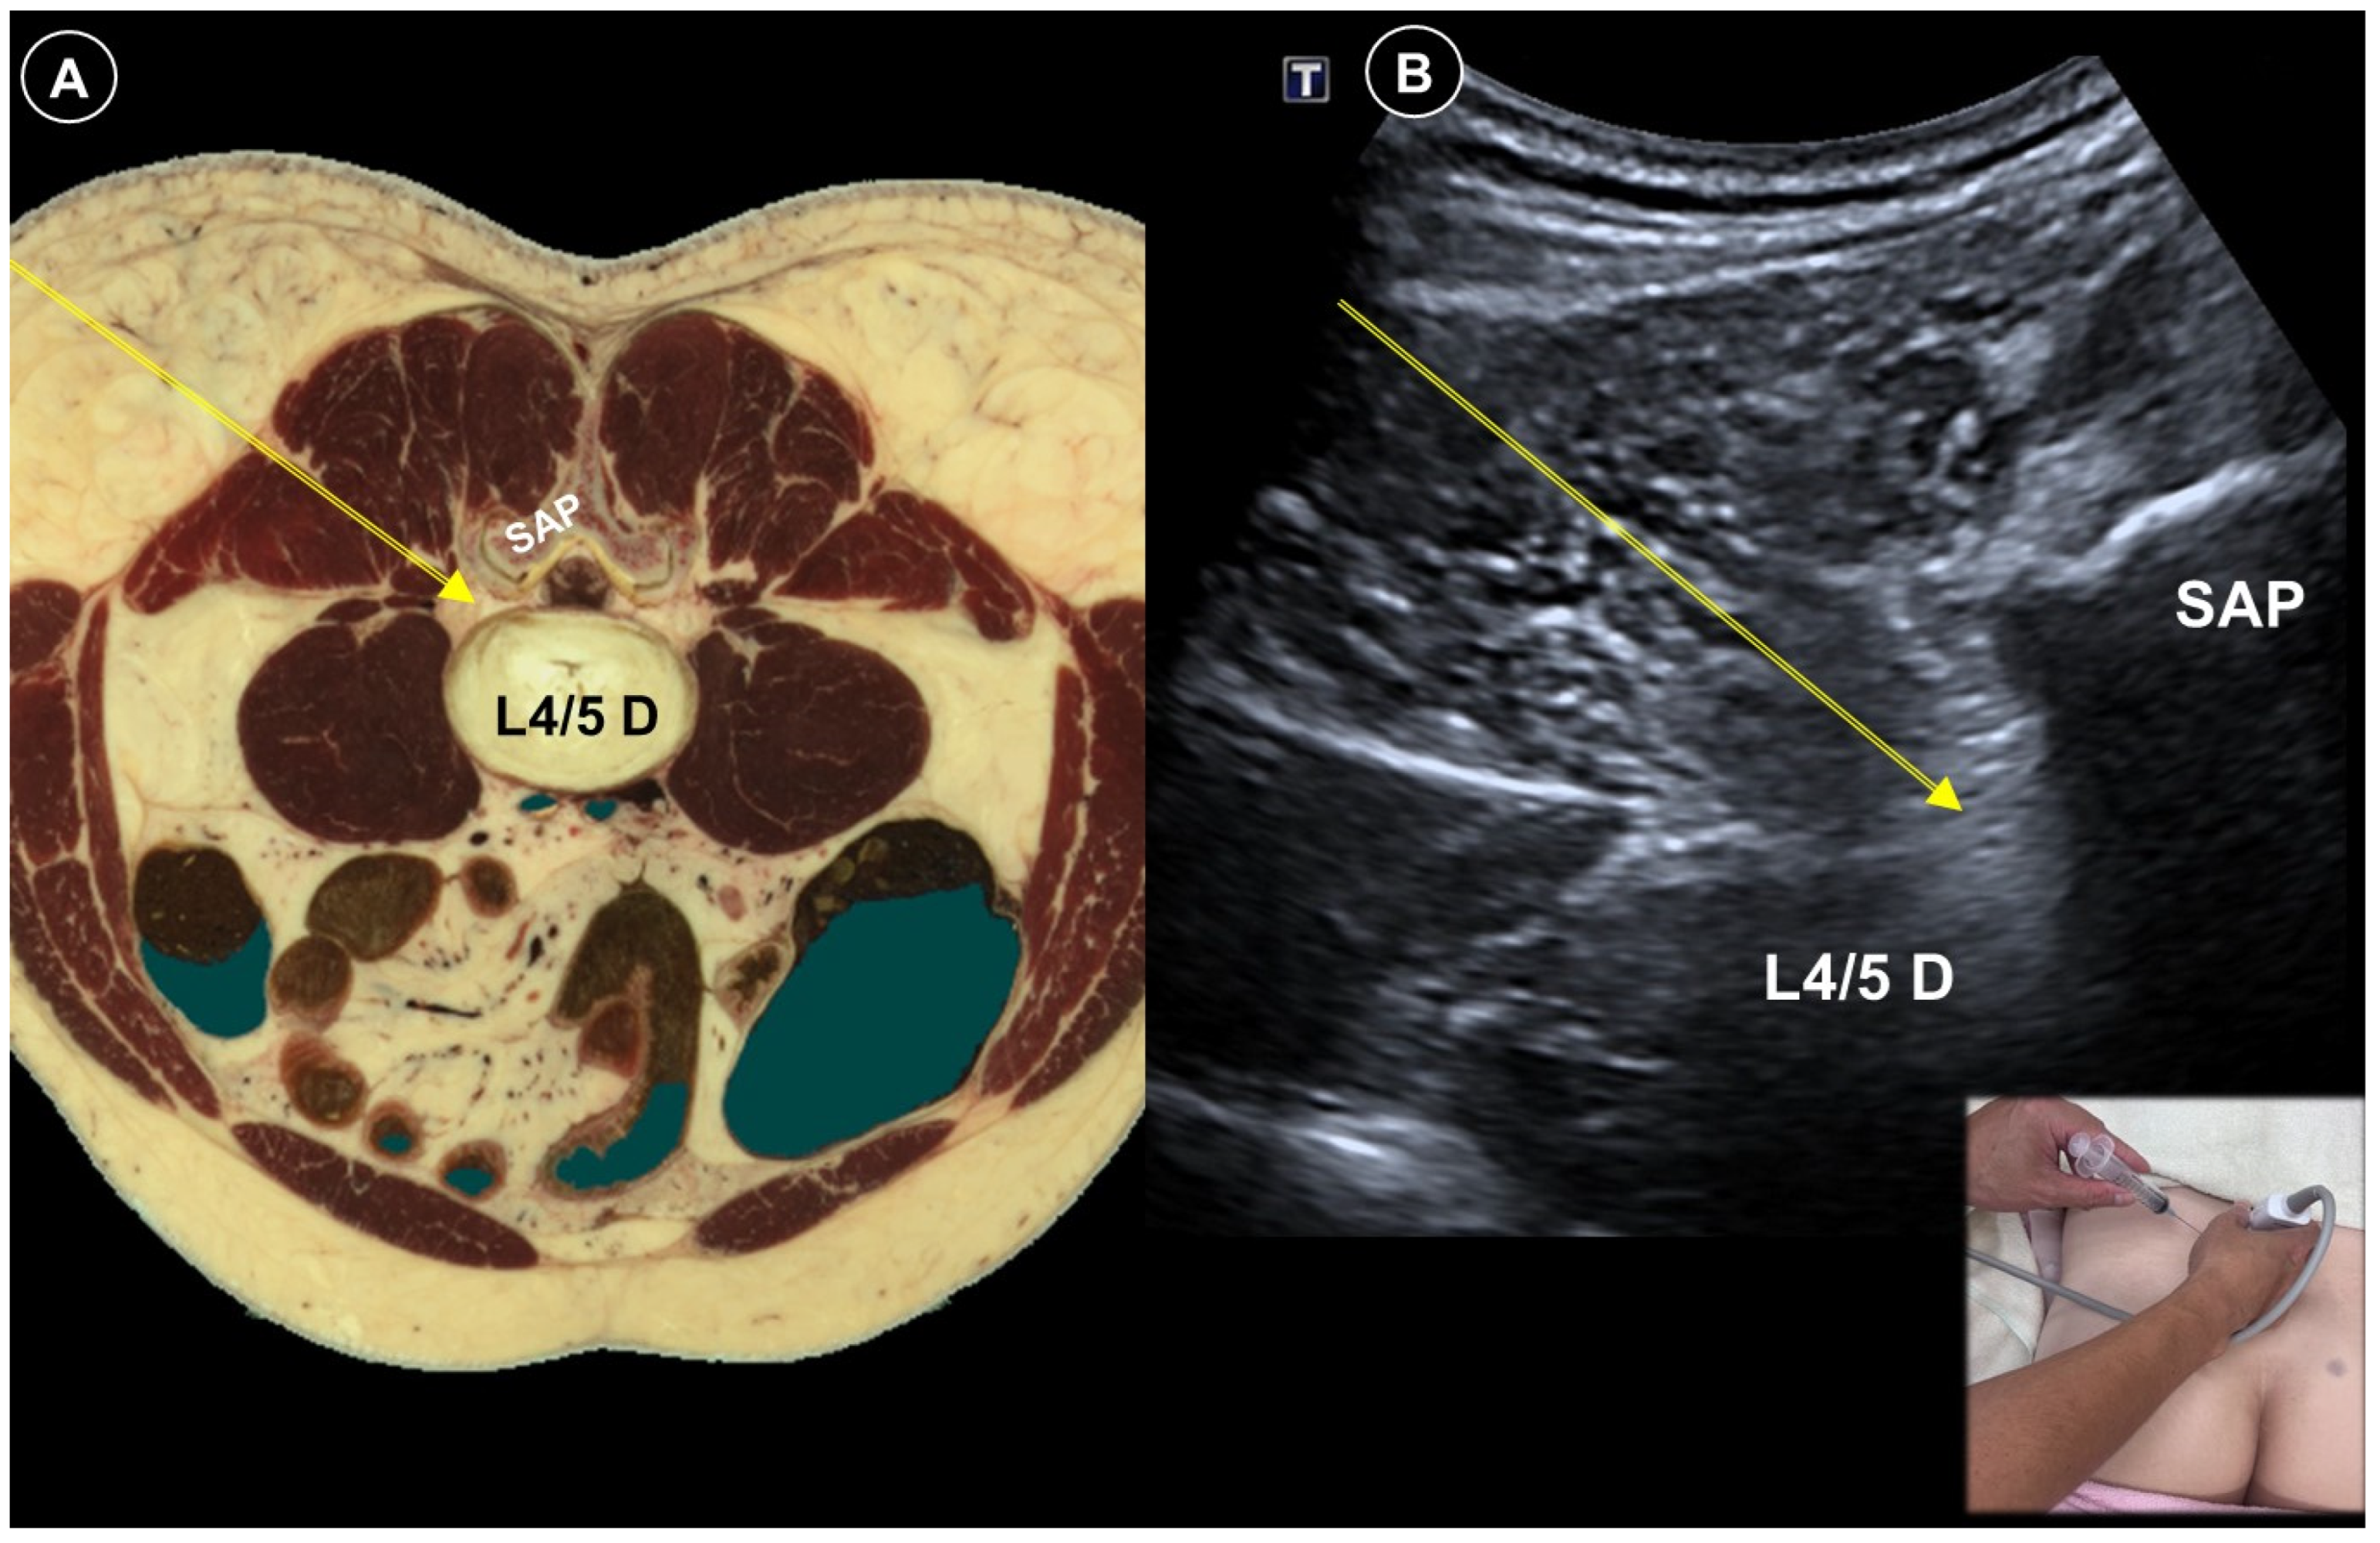

- Kim, Y.H.; Park, H.J.; Moon, D.E. Ultrasound-guided pararadicular injection in the lumbar spine: A comparative study of the paramedian sagittal and paramedian sagittal oblique approaches. Pain Pract. 2015, 15, 693–700. [Google Scholar] [CrossRef]

- Ortega-Romero, A.; Domingo-Rufes, T.; del-Olmo, C.; Ismael, M.-F.; Mayoral, V. Ultrasound-guided interventional procedures for lumbar pain. Tech. Reg. Anesth. Pain Manag. 2013, 17, 96–106. [Google Scholar] [CrossRef]